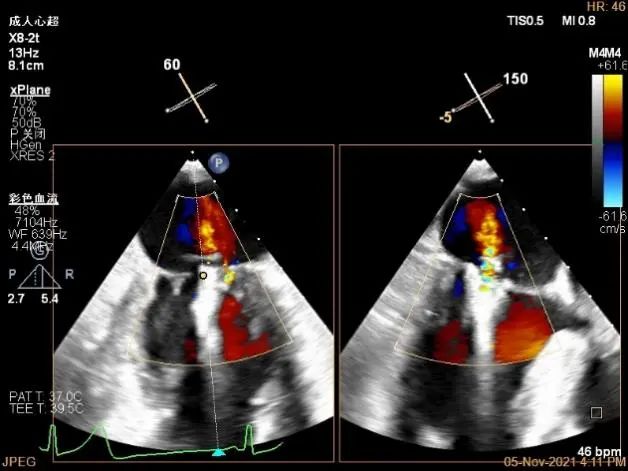

TEE Bicom view:主要脱垂区域为2区

Color-view:返流束主要来源于2区脱垂

夹子逐渐夹闭后,返流量逐渐减少

夹子放置后二尖瓣口平均跨瓣压差:1mmHg

肺静脉血流频谱恢复正向

夹子脱钩后,最终仅少量残余分流

3D-color:残余少量返流